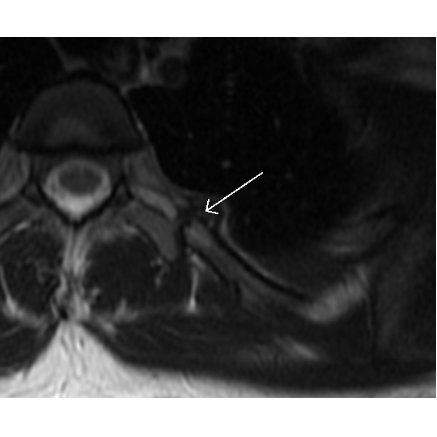

| Puzzling Periscapular Pain - Page #3 | |||